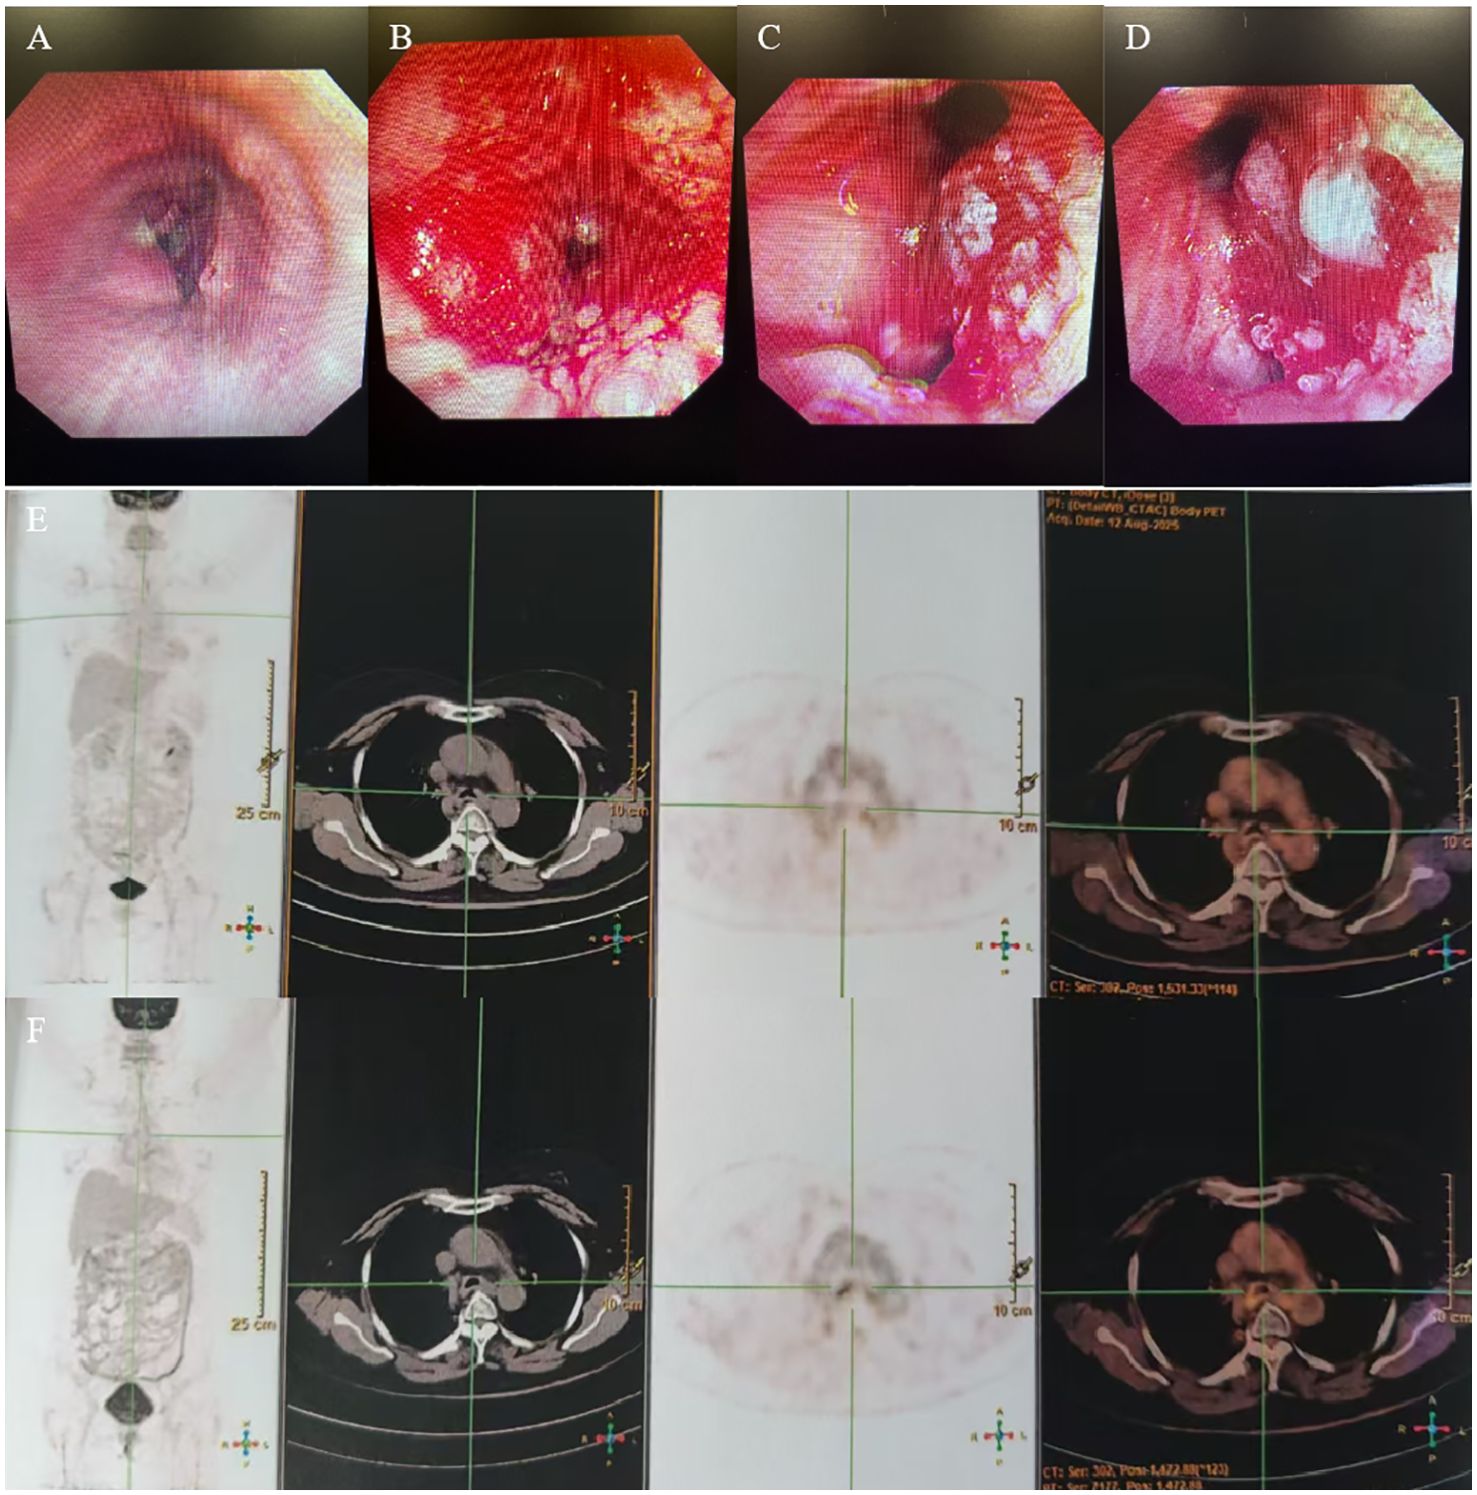

A 53-year-old woman presented with a history of more than 1 year of cough, coughing up phlegm, and shortness of breath for half a year, which worsened for half a month prior to her current presentation. Notably, she did not experience fever, thoracalgia, or any other relevant symptoms during that time. She denied any history of other diseases. The chest CT revealed the marked thickness of the lower segment and tracheal carina, leading to a locally narrowed trachea (Figures 3A, B). She had been hospitalized at local hospitals and received pharmaceutical treatment aimed at relieving her symptoms before her admission to our hospital. Regrettably, her shortness of breath did not yield with a significant relief. Subsequently, she was referred to our hospital for further medical assessment. After a whole-body examination was completed, there was no distant metastases found. The preliminary diagnosis pointed to an intratracheal mass. A fiberoptic bronchoscope verified a tracheal lesion situated 3 cm above the carina, and the lumen appeared notably narrow (Figures 4A–D). The pathological diagnosis of the biopsy was squamous epithelial high-grade intraepithelial lesion, with a tendency to be cancerous at the focal lesion. The tumor markers showed the following result: squamous cell carcinoma antigen at 2.74 ng/ml. The remaining examinations, as well as the laboratory examination, including routine blood, urine examinations, and those of the biochemistry examination, showed no abnormalities. The patient was diagnosed with tracheal SCC (cT4N1M0, stage IIIA) according to AJCC for lung cancer staging, but according to the classification proposed by Bhattacharyya, the stage was cT2N1M0, stage IIB. The surgery was difficult and risky, and radiation therapy was recommended. The patient received IMRT of true beam (Varian, USA). The target volume and radiation dose were as described in case 1 above combined with four cycles of chemotherapy of carboplatin plus paclitaxel (Figures 3E–H).

Figure 4. (A–D) Fiberoptic bronchoscopy showed a trachea lesion situated 3 cm above the carina, and the lumen appeared notably narrow. (E, F) PET/CT revealed the thickness of the tracheal carina, showing no 18-FDG uptake and without distant metastasis.

The patient had no obvious side effects during RT and recovered well. The CT result showed that the trachea lesion was markedly reduced at 1 month after RT (Figures 3C, D). She received four cycles of chemotherapy. At 6 months after RT, the chest CT still showed the thickness of the original tracheal lesion site, so a PET/CT was performed, which revealed the thickness of the tracheal carina and showed no 18-FDG uptake as well as without distant metastasis at nearly 9 months after RT (Figures 4E, F). Since then, she had undergone regular follow-up examinations every 3 months, and no symptom was reported. Her body movement though had returned to normal during the nearly 1-year telephonic follow-up. The patient provided written informed consent for the publication of the case details and the inclusion of accompanying images.